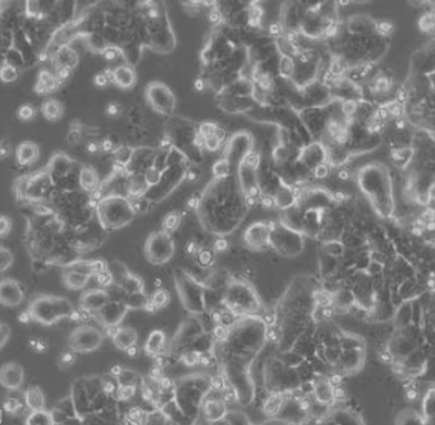

HCT-15细胞从一名男性Dukes C结直肠癌患者的大肠中分离出来。DNA指纹鉴定证据表明,DLD-1、HCT-15、HCT-8和HRT-18来源于同一个人,但同工酶及细胞染色体组型分析仍存疑问。HCT-15细胞呈CSAp阴性(CSAp-),角蛋白免疫过氧化物酶染色阳性。HCT-15细胞可用于3D细胞培养、高通量筛选、癌症和毒理学研究,也是一种合适的转染宿主。

上皮细胞样

贴壁生长